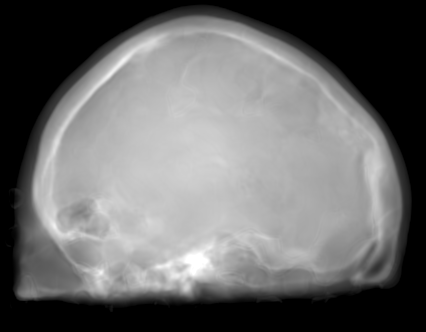

The proposed approach was successful in generating X-ray projections with a contrast similar to the one seen in true fluoroscopic X-ray images. Quantitative results of the generated projection images for all patients are presented in Tab. 2 and for the different network architectures in Tab. 2. In Fig. 2a to 2e the behavior of the MSE and SSIM w.r.t the projection angle is presented. Additional qualitative results of the proposed projection image-to-image translation pipeline for different patient data sets are shown in Fig. 3a to 3c. In Fig. 4 the influence of the modified network architecture, as well as the weighted loss w.r.t. to the edge map are presented.

MRI projection Generated projection Label projection

The improvement in our method compared to the baseline method is demonstrated by a decreased MSE, increased SSIM, and PSNR in Tab. 2. When examining Fig. 4a to 4c, improvements can be observed in the overall increased contrast of high-frequency details. Using the originally proposed architecture [5, 6], which gathers the residual blocks at the lowest resolution level, results in overall blurrier results and missing bone structures as seen in Fig. 4a. In contrast, the projections generated with the edge-weighted loss resemble the label images more closely. This can especially be observed at the base of the head. The projections created without the weighting also produce many high-frequency details in this region, however, these are less specific in comparison with the edge-weighted results. This results in decreased MSE and increased SSIM and PSNR of the projections synthesized using our approach. In addition, unnatural holes in the brain are generated by the baseline architecture. A possible explanation for the fluctuations in the error measure shown in Fig. 2a and 2b is that in our trajectory in the angles around 45 and 135 degrees the projection rays are cast from the side through the brain while around 90 and 180 degrees the angle of incidence is from the front or back side of the skull. In the first case this results in projections that exhibit large homogeneous areas which are easier to synthesize. In the second case, however, the high-frequency edges from the eyes, jawbone, etc. are the dominant structures in the image. A limiting factor of this study is the low number of patient datasets available. However, the amount of variation introduced by forward projecting the volumes is large. Varying projective geometries account for distinctively different structural appearance of the resulting projections. What is of course not covered by these transformations are unique characteristics of individual patients or different pathologies. To investigate the possible translation outcome of these properties larger datasets are required in the future. Also details that are not visible in the MRI projections can not be transferred to the generated images. An example would be interventional devices that are X-ray but not MR sensitive. Regarding subsequent post-processing applications, the question arises how this missing information in the generated projection images should be dealt with, which is subject to future work.